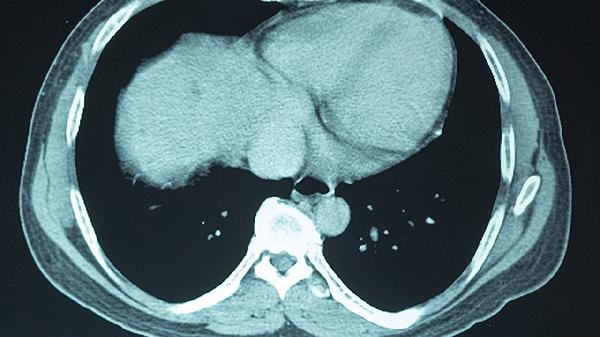

大脑供血不足患者日常应注意监测血压、血糖、血脂等指标,定期复查颈部血管超声或头颈部CTA评估血管情况。避免突然改变体位,防止跌倒。保持情绪稳定,避免剧烈运动和重体力劳动。如出现症状加重或新发神经功能缺损表现,应及时就医。饮食上可适量食用深海鱼、坚果等富含不饱和脂肪酸的食物,有助于维护血管健康。